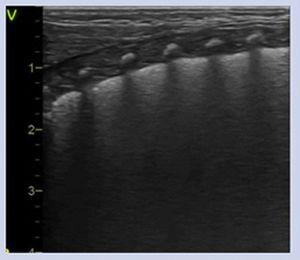

NeumotóraxLos signos ecográficos son: ausencia de deslizamiento de la línea pleural y de líneas B, con presencia exclusiva de líneas A5 y el punto pulmonar (PP), signo ecográfico que corresponde a la zona de transición entre el neumotórax (ausencia de deslizamiento pleural) y cualquier otro patrón pulmonar (deslizamiento pleural) (fig. 1. Video S5).

Neumotórax. A/ Plano longitudional anterior. Ausencia de deslizamiento de la línea pleural, ausencia de líneas B y líneas A muy definidas. B/ Modo M. Ausencia de deslizamiento. Signo de la estratosfera: línea pleural y líneas A equidistantes bien definidas. C/ Plano transversal 4-5° espacio intercostal. Punto pulmonar (PP): signo ecográfico que corresponde a la zona de transición entre el neumotórax (ausencia de deslizamiento pleural) y cualquier otro tipo de patrón pulmonar (deslizamiento pleural). Se considera neumotórax ecográficamente leve-moderado si el PP se localiza en línea medio clavicular o línea axilar anterior y grave, si se localiza a partir de línea axilar media.